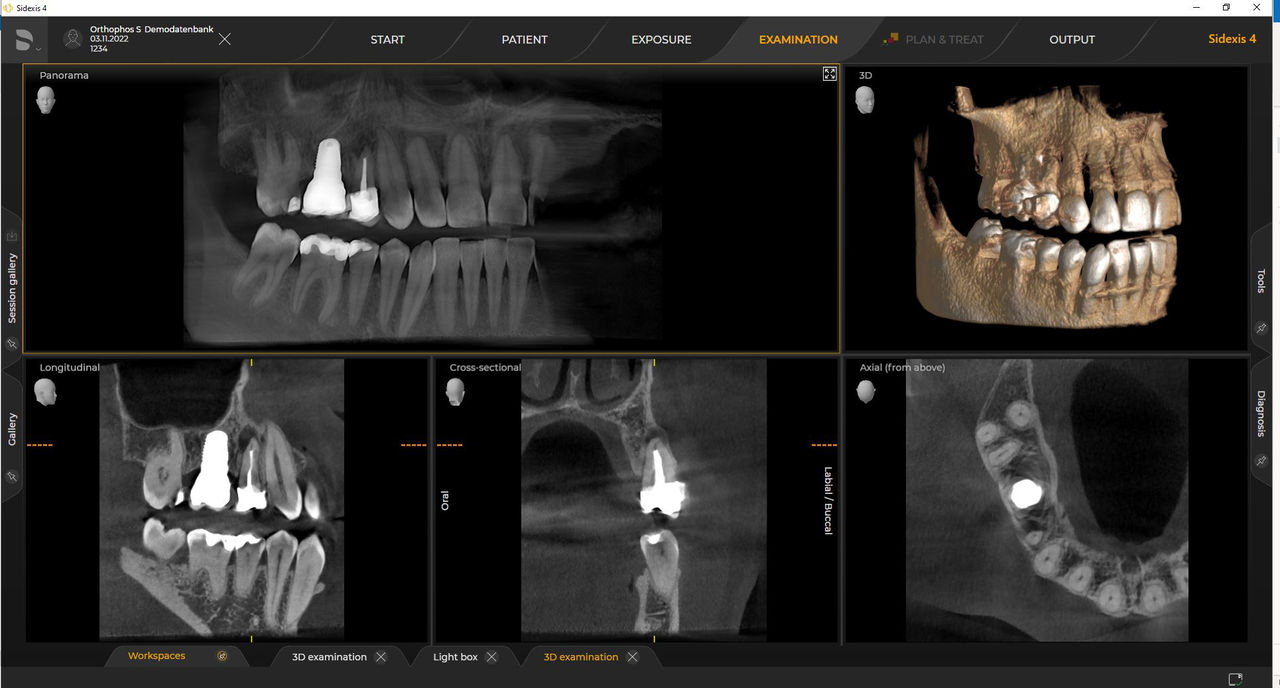

Las unidades de radiología de Dentsply Sirona funcionan exclusivamente con Sidexis 4. Sin embargo, la migración de datos de Sidexis XG a Sidexis 4 es muy fácil. Sidexis 4 permite una experiencia digital completa con las últimas herramientas